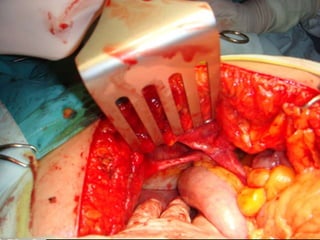

• Laparotomie mediana supraombilicala

- se evidentiaza sac de hernie epigastrica, de mici

dimensiuni, liber de continut;

- se practica reducerea colonului si a epipolonului in

cavitate peritoneala;

- se inchide defectul cu plasa de polipropilena;

- epiplonoplastie;

- drenaj – 1 tub abdominal;

- nu se excizeaza sacul herniar – aderente cu pleura

si pericardul;

- inchiderea peretelui cu fire separate, in 2 planuri.

Explorarea cavitatii peritoneale:

- orificiu de hernie diafragmatica retrocondrosternala

stanga cu dimensiuni de aproximativ 8/3 cm;

- ascensionarea 1/3 stang colonului transvers si

unghi splenic, cu mezocolon si epiplon in

hemitoracele stang;

- fara alte aspecte patologice intraperitoneale;

- fara alte defecte la nivelul diafragmului.